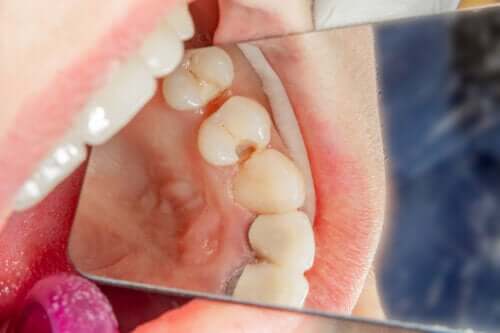

Soins dans les dents de lait avec caries

Lorsqu’il s’agit de soigner les dents de lait avec des caries, il existe différentes procédures en fonction des besoins du cas clinique particulier. Lorsque les caries commencent à peine, on peut avoir recours à des traitements de reminéralisation de l’émail. En revanche, si les lésions sont plus importantes et qu’il y a plus de perte de tissu dentaire, des plombages ou des couronnes seront nécessaires. De plus, si la carie a causé des dommages, il est nécessaire de recourir à des endodonties infantiles.

On n’a recours aux extractions dentaires que dans les cas où il n’est pas possible d’effectuer un traitement ou que les dommages à la dent présentent un plus grand risque pour l’enfant.